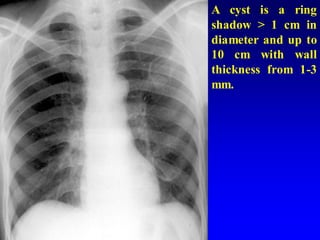

A cyst is a ring

shadow > 1 cm in

diameter and up to

10 cm with wall

thickness from 1-3

mm.